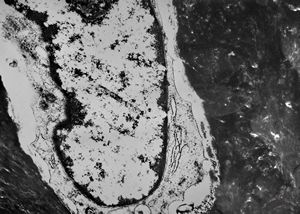

M,19y. | osteoid - chondrosarcoma - jaw

M,19y. | osteocyte - chondrosarcoma - jaw